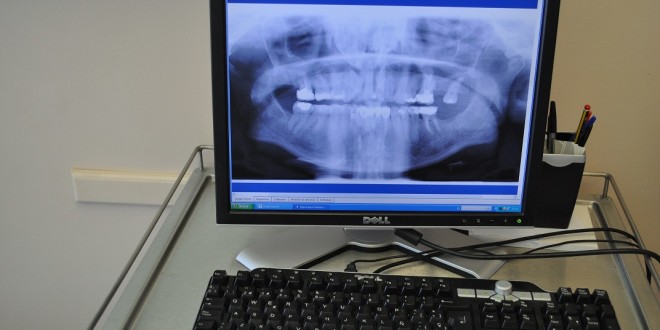

Hace algunos años tomar una radiografía de un diente era un proceso bastante complejo, que no sólo generaba desechos tóxicos, sino que también era muy lento y tenía que ser abordado por personal especializado. Hoy todos los centros asistenciales del Servicio de Salud Viña del Mar-Quillota cuentan con una red de radiología digital, que permite a los profesionales obtener estos valiosos exámenes médicos en forma rápida y limpia y visualizarlos en un computador para trabajar de manera más eficiente.

Así lo explicó el odontólogo Hernán Cifuentes, jefe del Departamento de Salud Oral del SSVQ, quien explicó que “hemos dejado atrás el antiguo y lento sistema de revelado de placas, que por años se utilizó en todos nuestros hospitales. Ahora, con estas unidades radiológicas digitales, podemos realizar una labor mucho más rápida e incluso consultar, a través de telemedicina, un diagnóstico con algún especialista en ortodoncia o implantes. Los usuarios se verán muy beneficiados con estos equipos, que son más caros que los tradicionales, pero que permiten un mejor trabajo”.